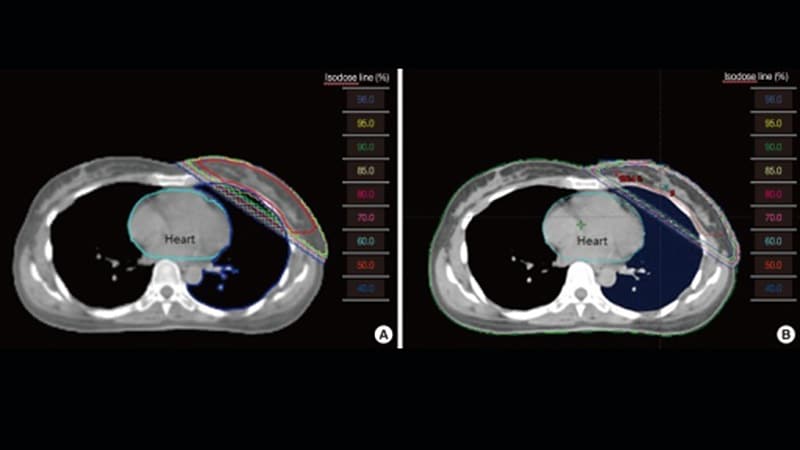

ASTRO Updates on Partial Breast Irradiation in Early Cancer

ASTRO Updates on Partial Breast Irradiation in Early Cancer -